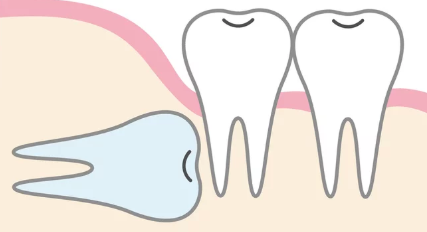

親知らずの生え方一例

親知らずの生え方はまず「歯肉や骨から見えているかどうか(埋まり具合)」と「傾き」によって分類されます。

近心傾斜(斜めに生えている)

親知らずの頭が、手前の歯(第二大臼歯)に向かって斜めに傾いて生えている状態で、歯の一部が歯ぐきから見えている「半埋伏歯」であることが多いです。

親知らずと隣の歯の間に深い隙間ができやすく、ここにプラークや食べかすが溜まり、最も頻繁に智歯周囲炎や虫歯を引き起こします。

抜歯の難易度は「中〜高」になることが多いです。